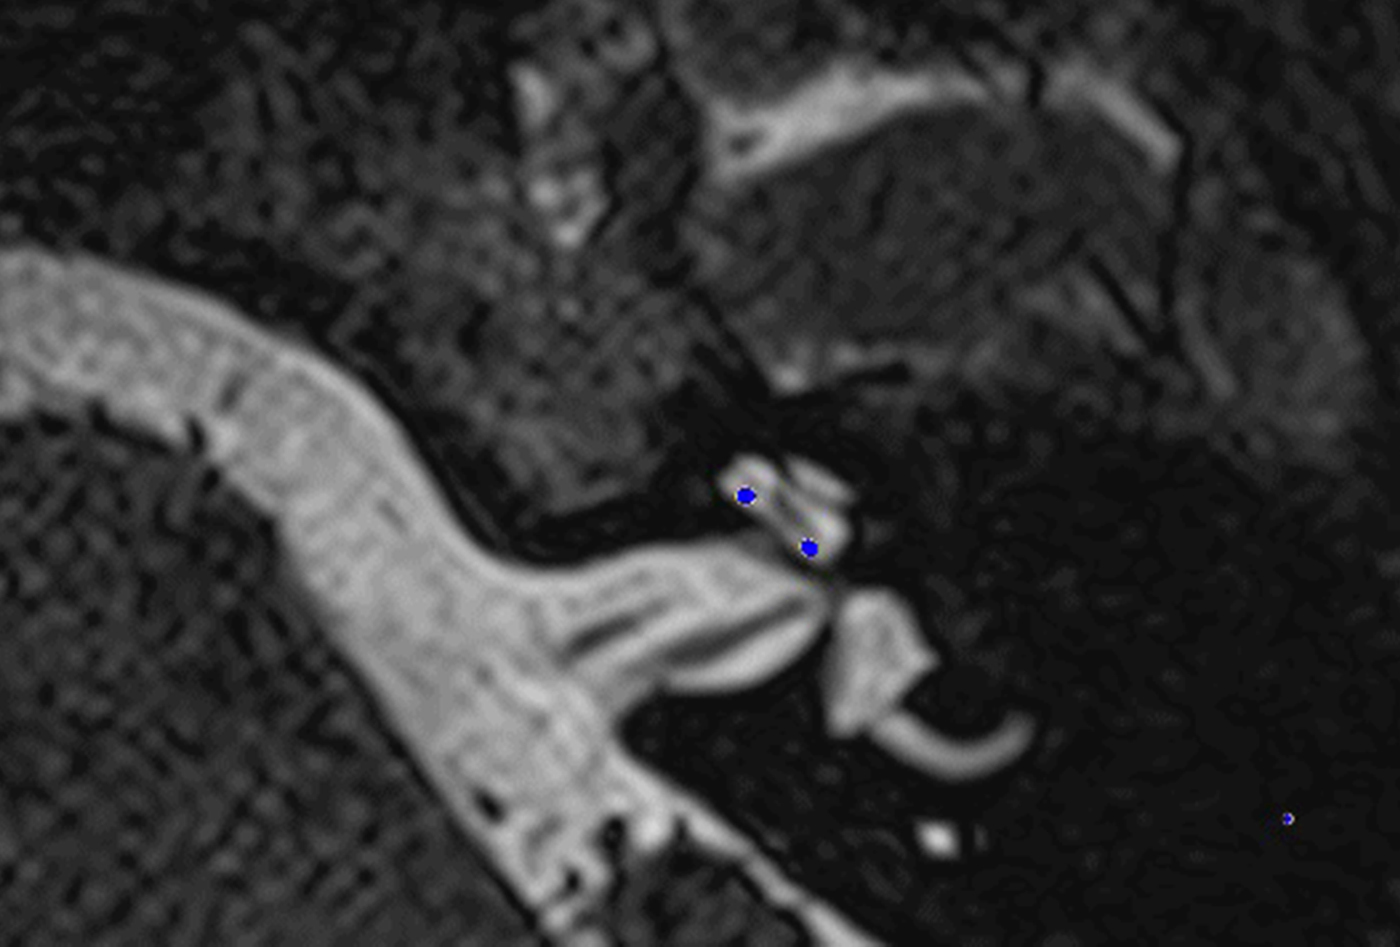

In these 19 cases, co-registration of the pre-operative MRI and post-operative cone-beam CT was performed, as described elsewhere.Reference Dragovic, Stringer, Campbell, Shaul, O'Leary and Briggs8 In short, the cone-beam CT and MRI scans were imported into the image analysis program Amira™ for semi-automatic registration. Three reference points on each image set were marked in three dimensions to allow automatic multipoint registration. The final registration was performed freehand, to ensure that the cochlea, vestibule and semicircular canals were aligned, with researcher satisfaction determining the final endpoint. This allowed accurate assessment of electrode position for these cases (Figures 1–3).

Fig. 1. Co-registered image of pre-operative magnetic resonance imaging and post-operative cone-beam computed tomography scans showing the electrode within scala tympani.